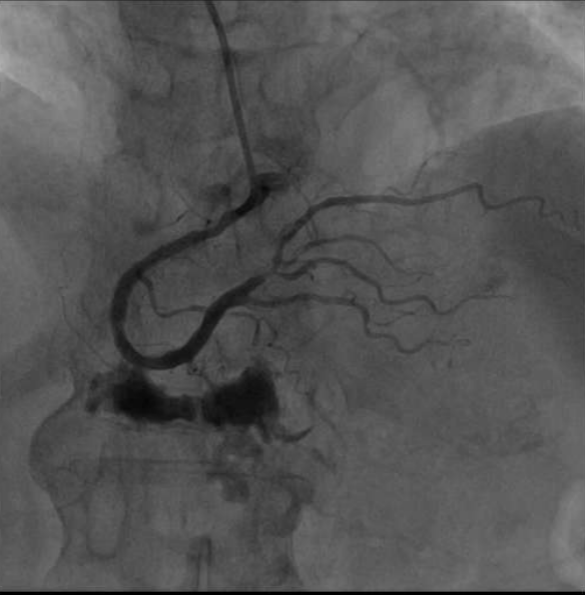

手术当天 , 李大娘顺利完成了冠脉造影检查 。 造影见左侧冠脉有很多斑块 , 但血管管腔狭窄尚不严重 。 右冠多处节段性狭窄 , 其中远段后侧支可见80%狭窄 。

看到这样的造影结果 , 大家都松了一口气 。 李大娘的确是因为右冠脉狭窄导致了下壁心肌梗死 , 但结合入院以来完善的血清学指标 , 已属陈旧性心肌梗死 。

造影见右冠脉远段仍有80%狭窄 , 属于临界病变 , 可先通过系统药物治疗来达到骨科围术期预防心脏风险的目的 。 目前可优先进行骨科手术治疗 。